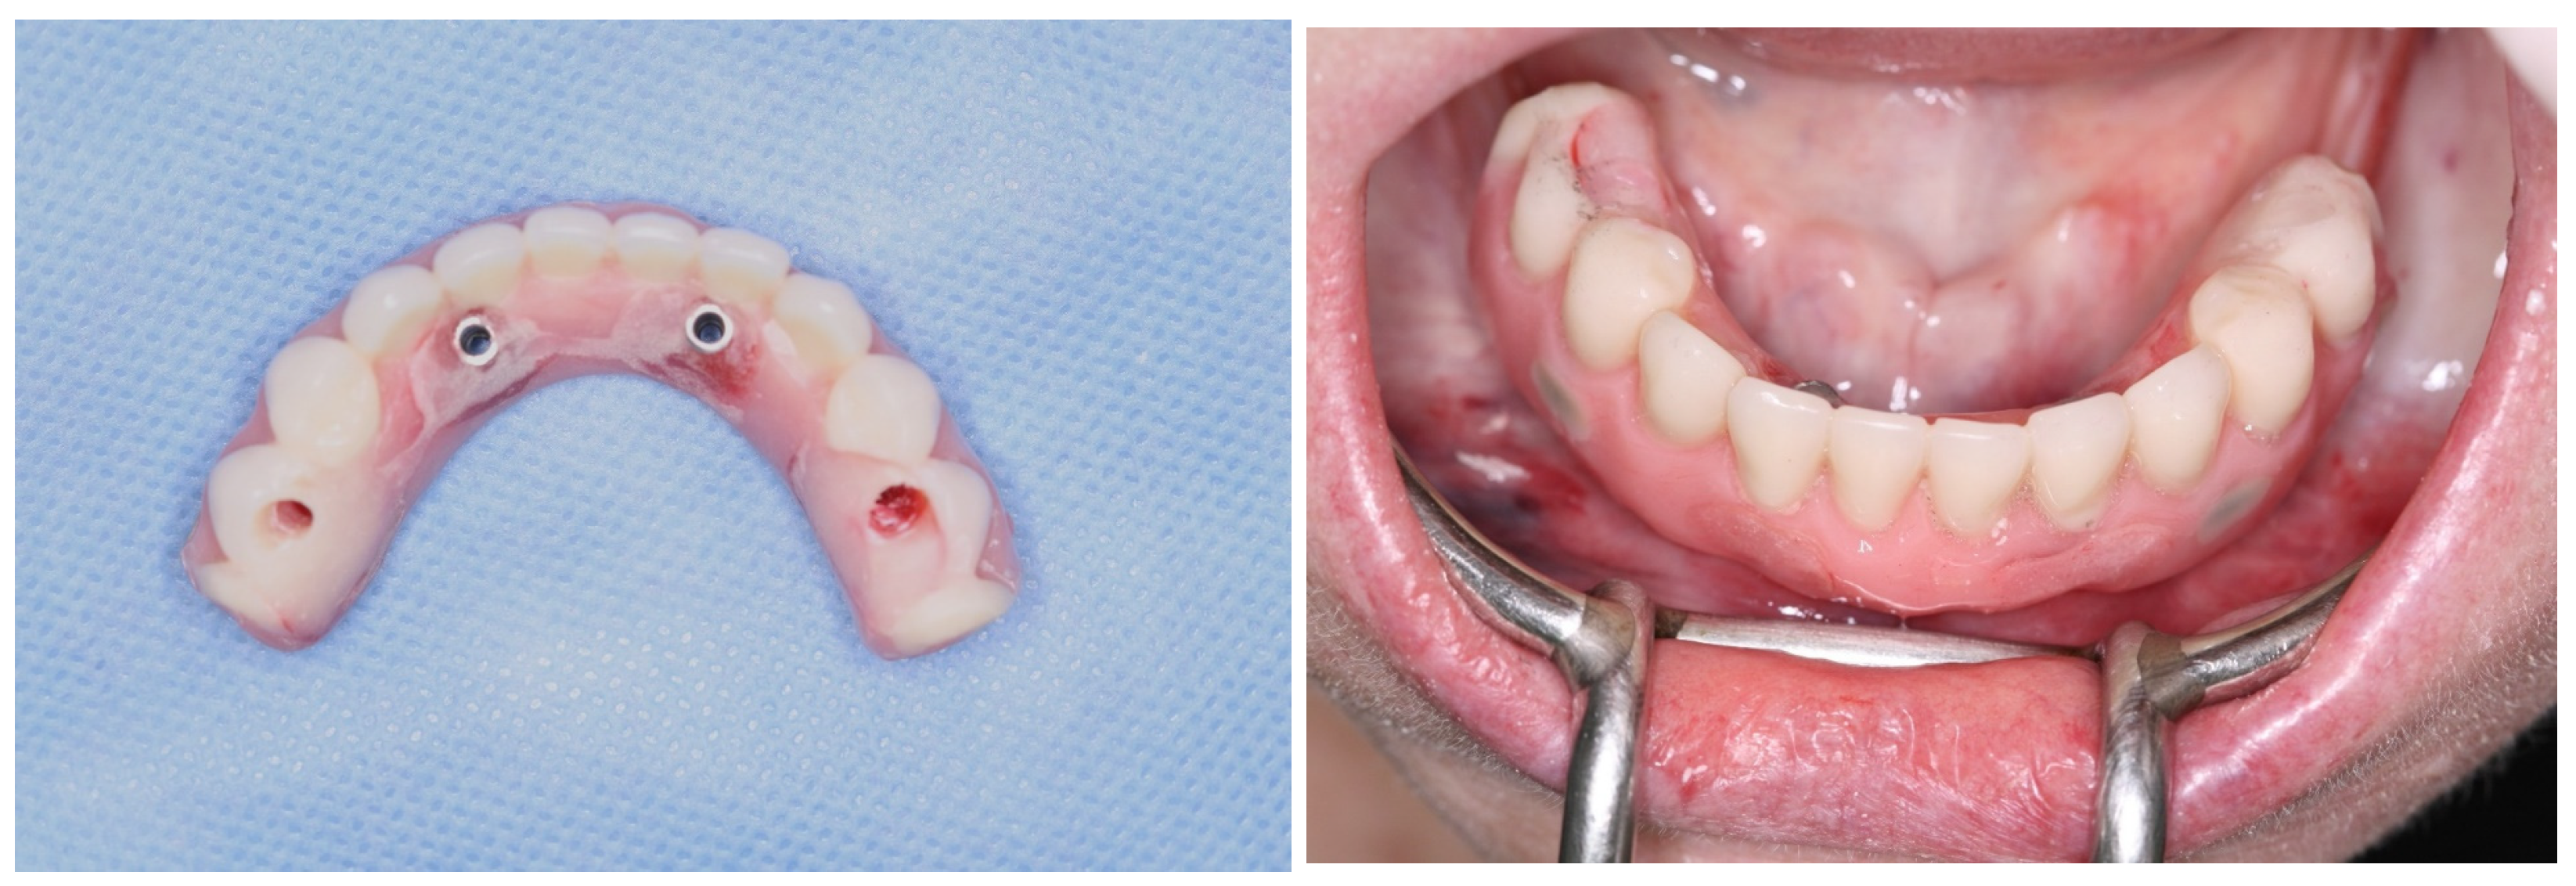

2. Case Report